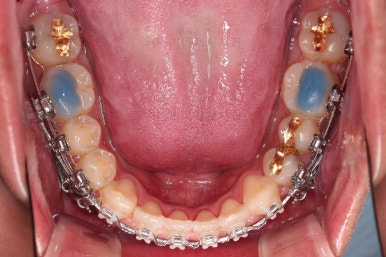

초진 시 입안의 모습입니다.

비교적 고른 편이긴 하나 아랫니가 전반적으로 밀려 나오면서 앞니끼리 부딪혀 있는 양상이고요.

어금니 맞물림도 긴밀하게 톱니바퀴처럼 위아래가 맞물려 있는게 아니라 엉성한 모습이죠.

앵글씨 3급 부정교합이라고 하는데요.

부산교정 장치를 부착했습니다.

이번에 선택하신 장치는 자가결찰 세라믹 장치에요. 스스로 철사를 묶는(결찰) 뚜껑이 달린(자가) 세라믹 성분의 장치인데요.

이번 환자분은 엠파워 클리어라고 하는 장치를 사용했으며 흔히 아신느 클리피씨와 동일한 계열의 장치입니다.

우선 치열이 가지런해졌으면 우리의 목표인 치열을 통째로 뒤로 미는 과정을 진행합니다.

잇몸뼈에 미니스크류라고 하는 아주 작은 임플란트를 식립하고요.

미니스크류를 이용해서 뒤로 당겨주게 됩니다.

어느 정도 아랫니가 뒤로 와서 위아래의 교합이 맞춰졌다 생각들면 윗니도 함께 뒤로 당겨줍니다.